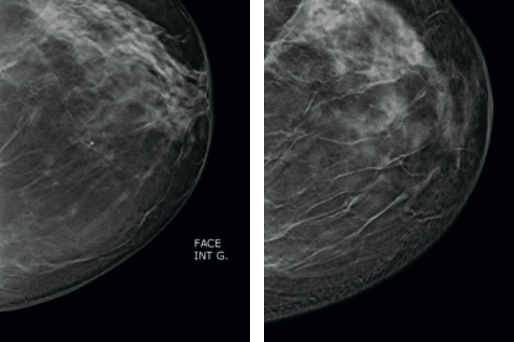

GYNECOMASTIE

La gynécomastie est un symptôme sans gravité à l’adolescence et elle régresse en général spontanément. La gynécomastie pathologique résulte d’un déficit androgénique ou d’une imprégnation estrogénique excessive : elle nécessite la recherche d’une cause endocrinienne, métabolique ou tumorale. DEFINITION La gynécomastie est un symptôme et non une maladie. Elle se définit comme hyperplasie des tissus…